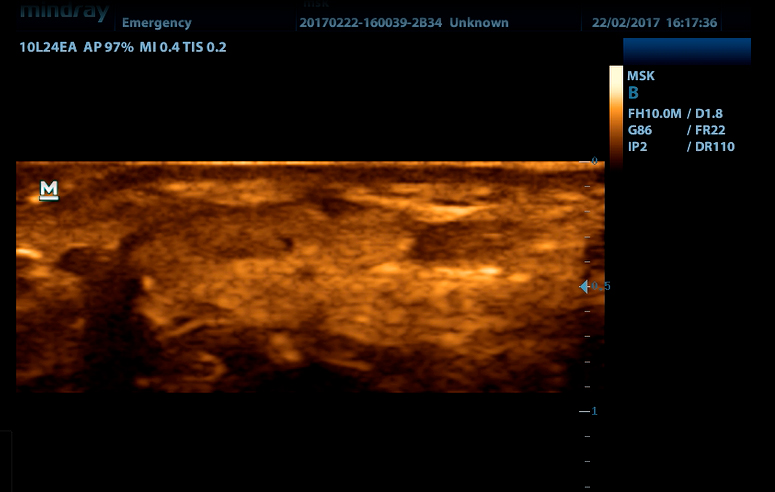

Портативный ультразвуковой сканер Mindray DP-50

Mindray DP-50 – портативная цифровая ультразвуковая система с ЖК монитором 15 дюймов (1024Х768)

и встроенными аккумуляторными батареями (опция) позволяющими работать в автономном режиме до 2-х часов.

Линейный датчик высокочастотный 10L24EA (8.0/10.0/12.0/14.0/Н10.0/Н12.0 МГц, 24 мм)